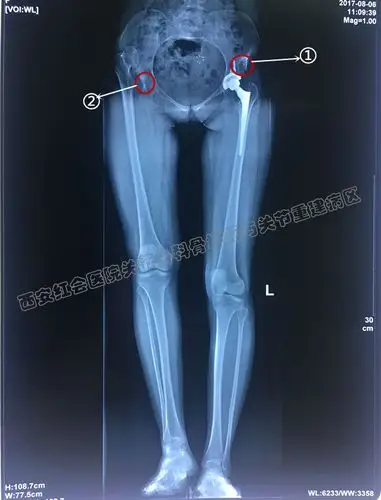

发育性髋关节发育不良并髋关节骨性关节炎典型病例